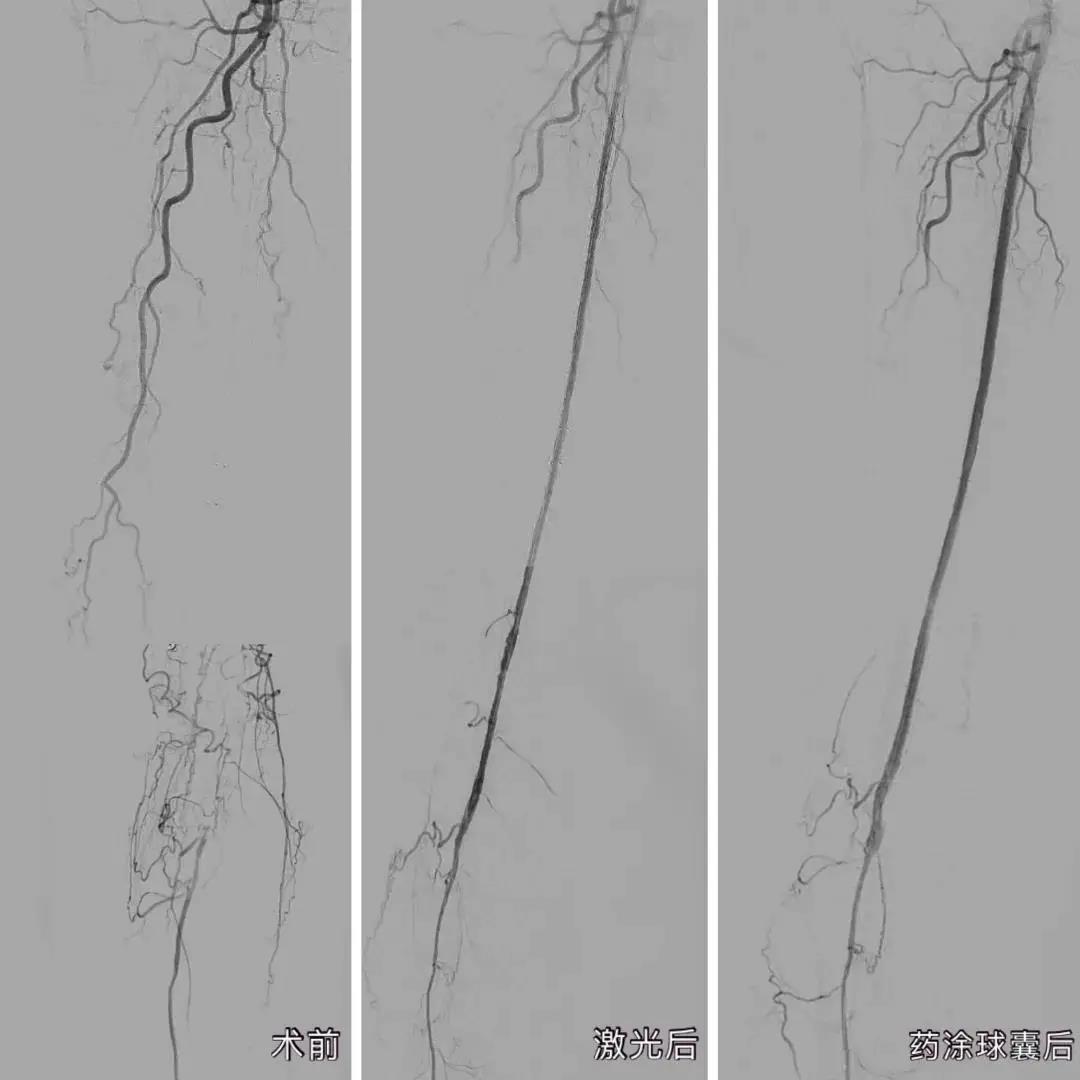

近日,华体会体育 血管外科利用“准分子激光消蚀技术”联合“药物涂层球囊”技术,成功让这名双下肢动脉硬化闭塞患者的血管恢复通畅。

经过完善的术前准备,庄晖主任率团队在患者大腿的动脉,穿刺了一个仅绿豆般大小的口子,将激光导管从小洞中引入到堵塞的血管中,用准分子激光进行开通。仅是激光消蚀减容还不够,医生又使用了药物涂层球囊,通过球囊扩张,将一种防止内膜增生的药物涂到血管内壁上,从而达到长期抑制血管再狭窄的效果,“通俗来说,就是起到防止血管内再长‘水垢’的作用。”

手术过程顺利,术后造影结果下肢动脉病变部位全程血流通畅。经过华体会体育 护理团队的细心看护,郑奶奶手术后第二天就可以下床活动,术后不到一周便解除了疼痛,完全正常行走。